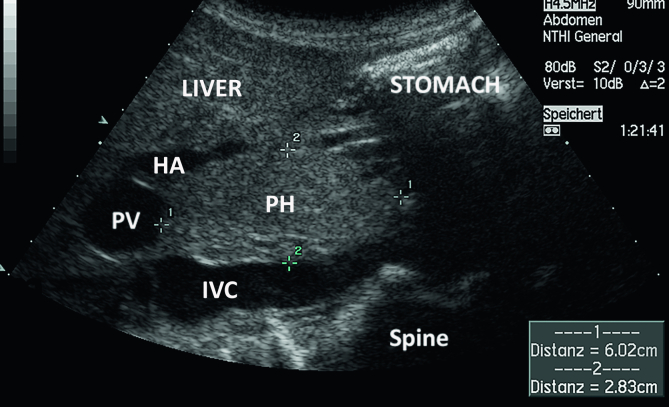

Reliable and reproducible measurement methods have been established, and reference values are used in almost all scientific disciplines. Knowledge of reference values is crucial to distinguish physiological from pathological processes and, therefore, subsequently, for the clinical management of patients. Image storage and documentation of measurements and normal findings should be part of quality assurance in imaging. This paper aims to review the published literature and provide current knowledge of sonographic measurements and reference values of the pancreas. Moreover, the role of clinical influencing factors such as age, gender, constitution, and ethnicity is also analyzed.